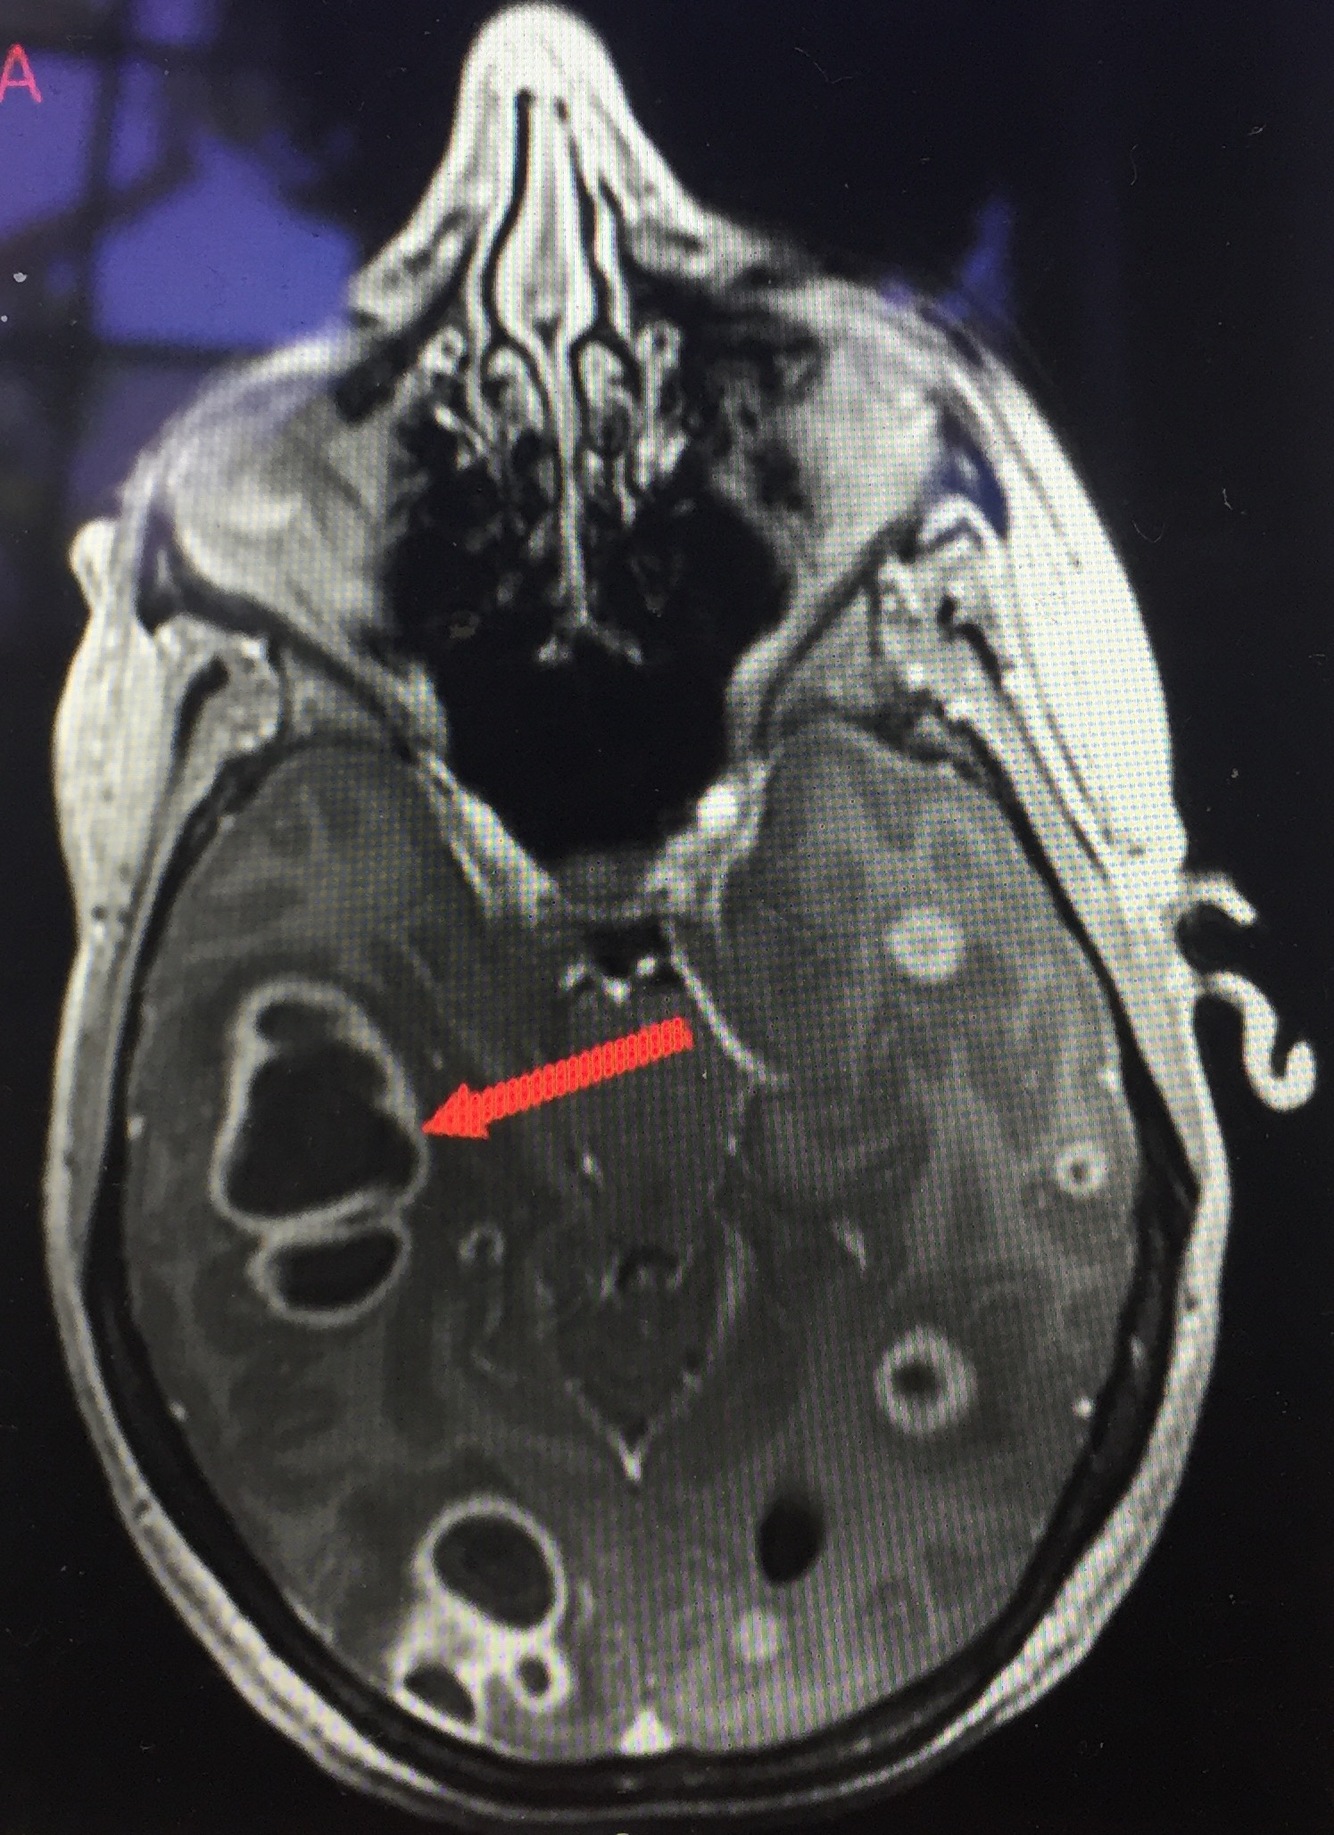

Gadolinium-enhanced brain MRI

Used to diagnose brain abscess

Brain abscess